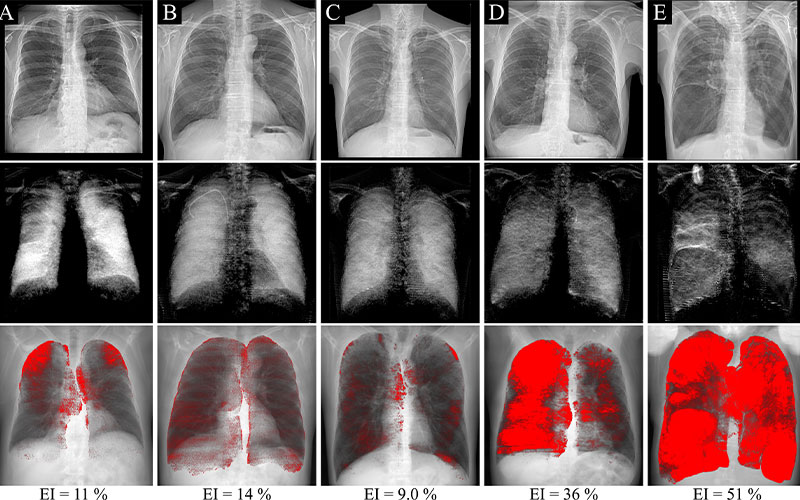

Attenuation-based (top row) and dark-field (middle row) radiographs and projections of CT-based emphysema quantification (bottom row) in five example participants with a significant emphysema index (EI) of 6% or more. The same window and level settings were applied within each respective modality. Signs of hyperinflation can be observed in attenuation-based images of participants with high emphysema severities. Areas of decreased dark-field signal correspond well to emphysematous areas on the CT-based emphysema projections. In B, the participant has a right-sided port catheter in place.

On a dark-field image, a healthy lung appears in uniform, bright white, due to intact alveolar structures that create a strong dark-field signal. The opposite occurs in a dark-field image of emphysematous lungs and is very apparent to the naked eye.

“In a healthy lung, the alveolar structure has many tissue interfaces, each of them causing a small change of direction in the beam that results in a strong scattering signal, or dark-field signal,” Urban said. “When there is some impairment of the alveolar structure, then there are fewer air-tissue interfaces, and therefore a weaker dark-field signal. In a dark-field image, this appears as dark patches on the lung.”

The appearance of their lungs was also examined using both attenuation-based and dark-field radiography. Dark-field images were then compared to CT images to test any visual correlations of CT-based emphysema findings. This comparison showed that the locations of signal intensity loss on dark-field images corresponded to emphysematous areas found on CT.

“The emphysema detected in CT corresponds very well to the dark patches in the dark-field images. This tells us that the dark-field signal is accurate, and that it is sensitive to emphysematous changes of the lung,” said Urban.